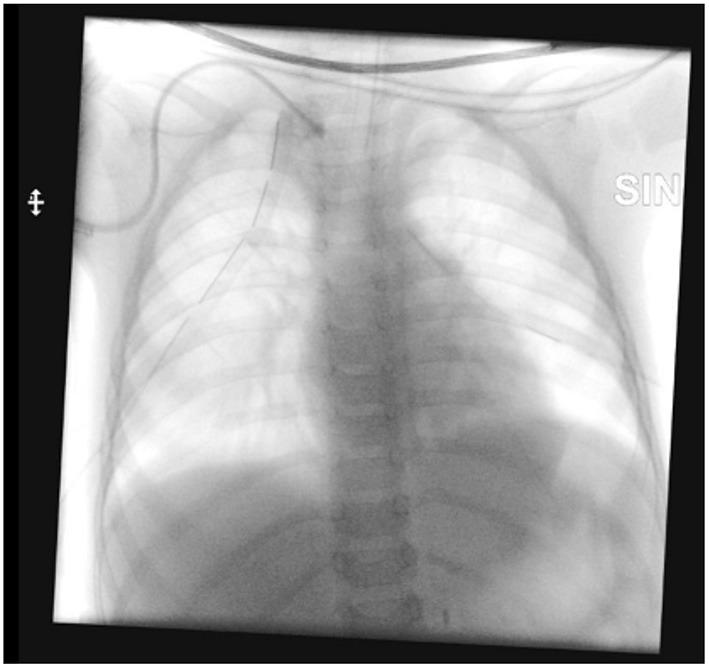

The insertion of long-term central venous catheters is a standard of care for children affected by malignancies, although it can be associated with life-threatening complications. The present paper reports an unusual mechanical complication related to the use of a long term tunneled central venous catheter in a pediatric oncologic patient. An 18 months old child, diagnosed with stage M high-risk retroperitoneal neuroblastoma, underwent ultrasound-guided placement of a 6 Fr bilumen long-term tunneled central venous catheter in the right internal jugular vein prior to the beginning of induction chemotherapy. The correct position of the distal tip of the catheter was confirmed by fluoroscopy. After 4 months of regular use of the device, the patient experienced neck swelling during high-dose chemotherapy infusion. A chest x-ray showed a dislocated catheter and bilateral pleural effusion. CT scan demonstrated the tip of the catheter rupturing the medial wall of the right jugular vein and entering the mediastinum; furthermore, pneumomediastinum, subcutaneous neck emphysema and bilateral pleural effusion were noticed and a thrombus was evident in the right jugular vein at the insertion in the brachiocephalic vein. The patient was then transferred to the Intensive Care Unit and bilateral thoracostomy tubes were placed urgently (500 mL of clear fluid were evacuated from pleural spaces). The dislocated catheter was removed electively on the following day under fluoroscopy. Despite ultrasound-guided placement and long-term uneventful use of the catheter, life-threatening central venous catheter-related mechanical complications can occur; the current case report emphasizes the importance of careful monitoring of patients with central venous catheters in order to quickly diagnose and treat potentially lethal complications.

长期中心静脉导管的插入是治疗恶性肿瘤患儿的一项标准护理措施,尽管它可能会伴有危及生命的并发症。本文报告了一例与儿科肿瘤患者使用长期隧道式中心静脉导管相关的罕见机械并发症。一名18个月大的儿童,被诊断为M期高危腹膜后神经母细胞瘤,在诱导化疗开始前,于右侧颈内静脉接受了超声引导下的6F双腔长期隧道式中心静脉导管置入。通过荧光透视确认了导管远端的正确位置。在该装置正常使用4个月后,患者在高剂量化疗输液期间出现颈部肿胀。胸部X光显示导管移位及双侧胸腔积液。CT扫描显示导管尖端穿破右侧颈静脉内侧壁并进入纵隔;此外,还发现了纵隔气肿、颈部皮下气肿和双侧胸腔积液,且在头臂静脉插入处的右侧颈静脉中有明显血栓。随后患者被转入重症监护病房,并紧急放置了双侧胸腔闭式引流管(从胸腔抽出500毫升清亮液体)。次日在荧光透视下选择性地取出了移位的导管。尽管导管是在超声引导下置入且长期使用无异常情况,但仍可能发生危及生命的与中心静脉导管相关的机械并发症;本病例报告强调了对中心静脉导管患者进行仔细监测以快速诊断和治疗潜在致命并发症的重要性。